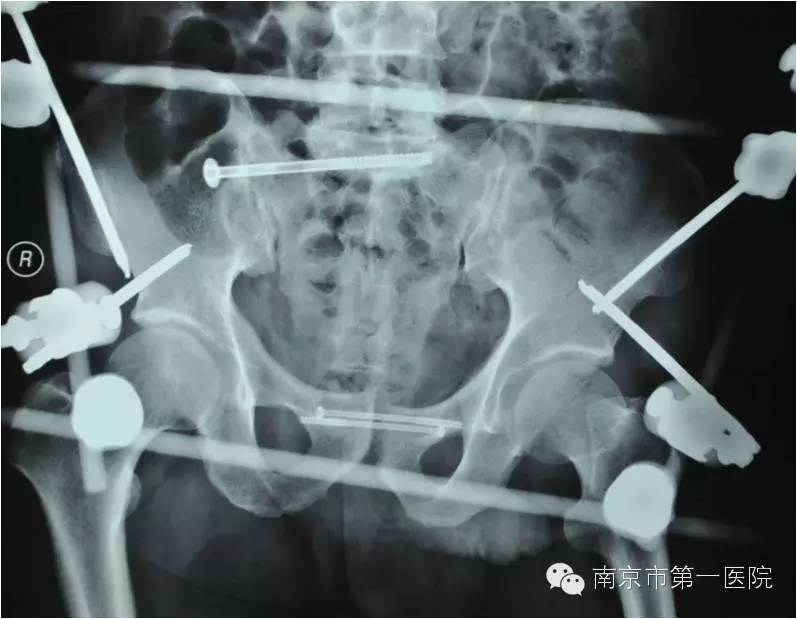

我院骨科专家梁斌接到通知后,开通多发伤绿色通道,迅速召集科内骨干医生进行术前讨论、制定手术计划。考虑到患者创伤严重、出血量大,必须最大程度地减少手术伤口,梁主任决定立刻采取微创技术进行骨盆闭合复位支架外固定术。

术中,主刀医生操作技术娴熟,争分夺秒,有条不紊地进行着各项操作。经过1个小时,手术顺利结束,成功修复了患者重度骨折的骨盆。据悉,整个手术过程中,创伤小、出血量低,切口大小也仅有1-2cm左右。

随后,老张第一时间被送到当地医院进行了简单处理,处理完又立刻转到南京市第一医院进行进一步抢救。据了解,小卡车大约1.5吨重,受伤的部位在骨盆,由于受到碾压和挤压,导致骨盆内的肌肉撕裂、血管损伤,骨盆也粉碎性骨折。另外,同时存在右侧胫腓骨粉碎性骨折及大面积软组织损伤。